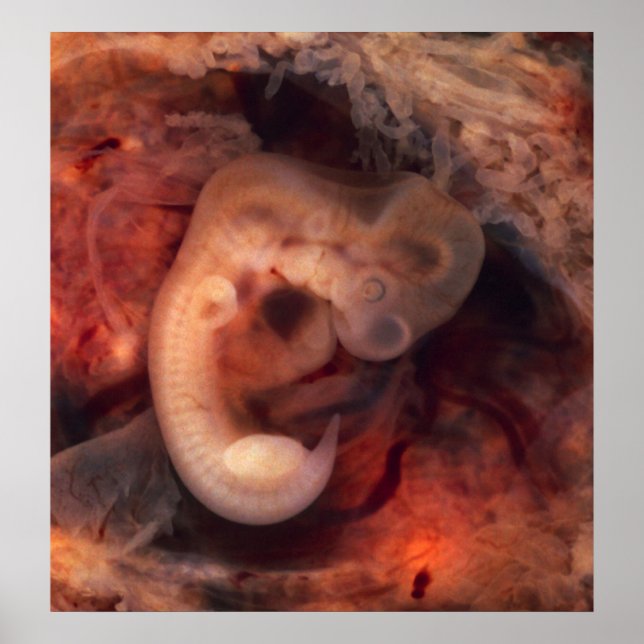

Human Embryo 7:e Vecka Gravid 5th Peek P. O. Poster

Humanembryo (7:e vecka av gravid, 5 veckor per år) Detta foto av en öppen ovidukt med en ektopisk gravid har ett spektakulärt välbevarat 10 millimeter embryo. Det är ovanligt att se ett embryo över huvud taget i ett ekovarium, och att man ser detta väl bevarat (och ostört av proktorns knivar). Till och med ett embryo av detta lilla slag uppvisar mycket tydliga anatomiska egenskaper, bland annat svan, kroppsknoppar, hjärta (som faktiskt skjuter ut från bröstet), öga kopp, hornhinnor/lins, hjärna och framträdande segmentering i somiter. Ggestationssac omges av en myriad av korionvilli som liknar långvanda party-ballonger. Detta embryo är ungefär fem veckor gammalt (eller sju veckor i det biologiskt missvisande men i högsta grad praktiskt tillämpbara modersmjölksersättningssystem som används vid obstetrik). Anmäl dig till Rebates for FREE and spara 12% på valfri zazzle-beställning utöver en registreringsbonus på 5,00 USD Alla Höger Reserverade; utan förutfattade meningar, regress eller meddelande (U.C. 1-308) http://en.wikipedia.org/wiki/File:Tubal_Pregnancy_with_embryo.jpg embryografisk gravid från människa till baby.